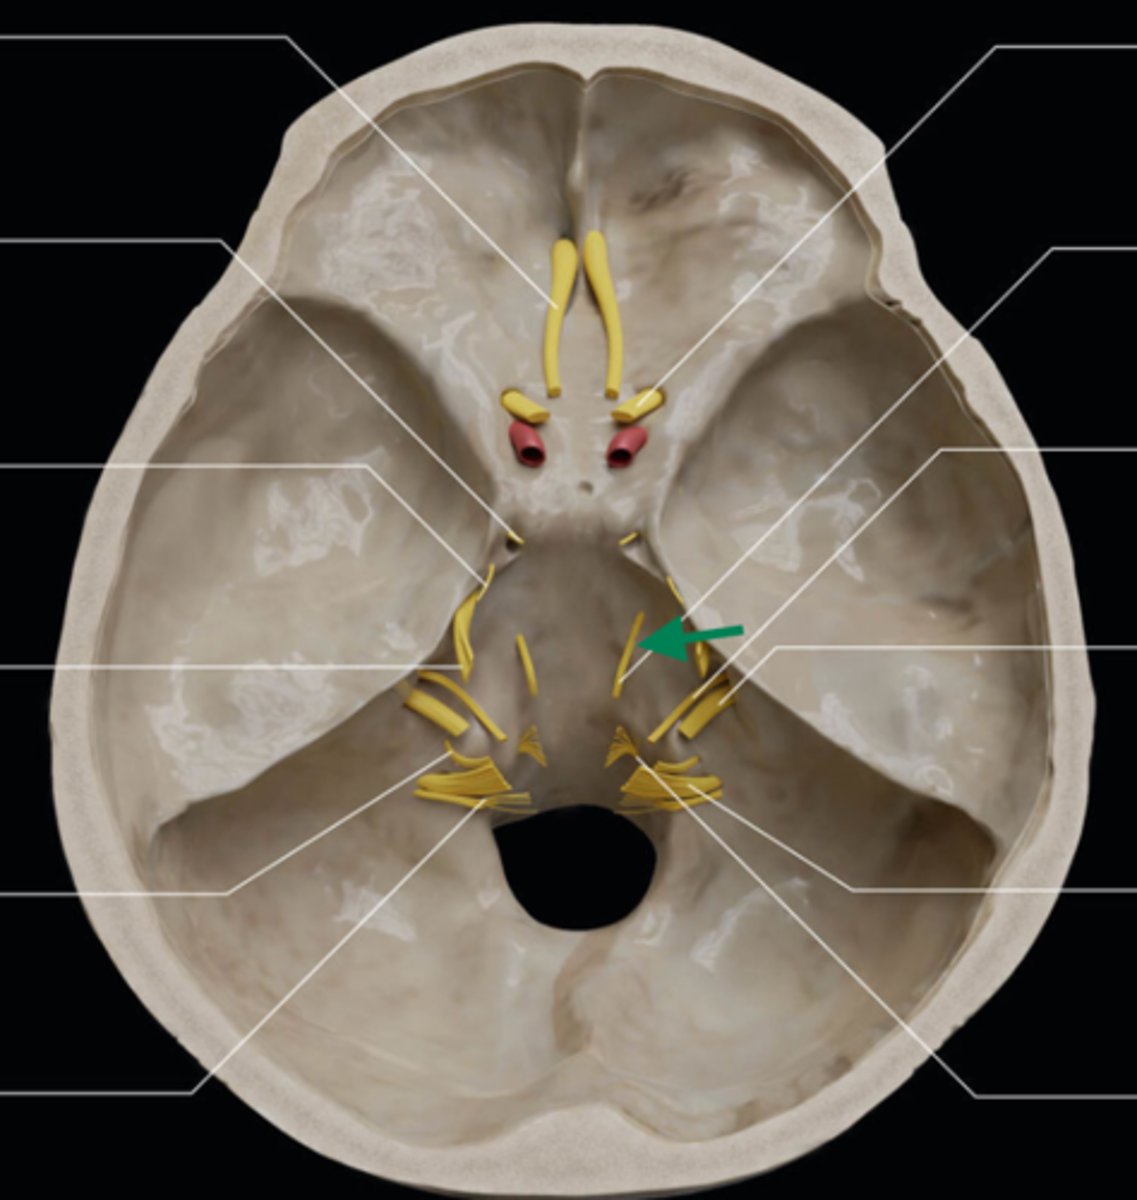

olfactory bulb

olfactory tract

optic nerve (CN II)

internal carotid artery

oculomotor nerve (CN III)

trochlear nerve (CN IV)

abducent nerve (CN VI)

trigeminal nerve (CN V)

facial nerve (CN VII)

vestibulocochlear nerve (CN VIII)

glossopharyngeal nerve (CN IX)

vagus nerve (CN X)

accessory nerve (CN XI)

hypoglossal nerve (CN XII)

optic chiasm

trigeminal ganglion

anterior cranial fossa